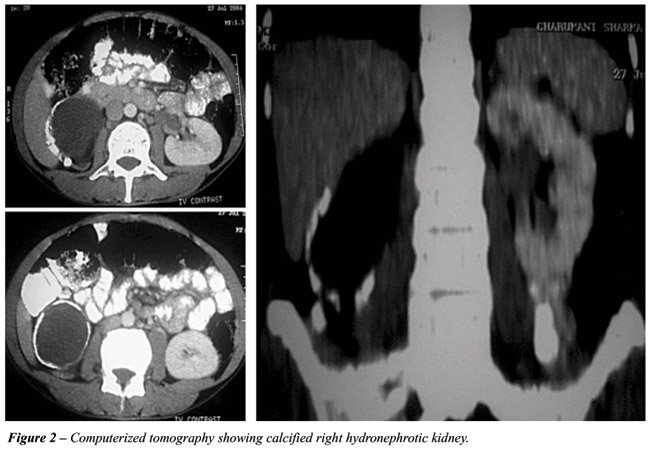

A thirty-year-old man was investigated for abdominal pain and a palpable mass in the right lumbar region. He had no associated urinary symptoms or bowel dysfunction. The only significant history was a pulmonary tuberculosis ten years before for which he was adequately treated. He had no history of any operative intervention or trauma in the past. On physical examination, he was normotensive and had a 7cm hard, nontender bimanually palpable lump with restricted mobility in the right lumbar and umbilical region. No bruit was present over the lump. An investigation revealed a normal urine routine and microscopic examination, sterile urine culture and a normal hemogram. Serum creatinine, blood urea nitrogen and serum calcium were unremarkable. Urine for acid-fast bacillus microscopy was negative thrice and urine polymerase chain reaction for Mycobacterium tuberculosis was also negative. Indirect hemagglutination test for hydatid was negative. KUB film revealed an eggshell like calcification in the right kidney region (Figure-1). Subsequent ultrasound and computerized tomography showed a well defined, cystic right kidney (Figure-2). Renal scan confirmed the absence of any functional renal parenchyma on the right side. On cystoscopy, the right orifice was normal and no urine flow was detected. Right retrograde pyelogram revealed a thin ureter, which was obstructed at the ureteropelvic junction. Laparoscopic nephrectomy was done. Multiple sections examined showed a fibrocollagenous cystic wall with hyalinization, calcification and ossification. Certain areas with intact epithelial lining and thyroidization of renal tubules were also observed. No granulomatous inflammation or parasite was present.